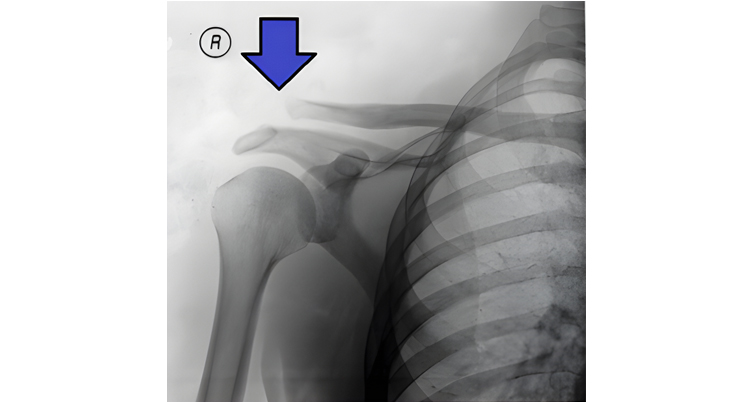

X-ray demonstrating acromioclavicular joint separation. Jay F. Cox, Wikimedia Commons, 2006. Licensed under CC BY 2.5.

AC Joint Injuries and Arthritis

What is it: The acromioclavicular or AC joint is located at the top of the shoulder where the collarbone meets the shoulder blade. Injuries to this joint often occur after a fall directly onto the shoulder. Arthritis of the AC joint may also develop over time due to repetitive stress or aging.

Symptoms: AC joint issues commonly cause pain on the very top of the shoulder. Discomfort is often noticeable when reaching across the body, lifting objects, or performing pressing movements.

What to do: Treatment focuses on restoring shoulder strength and movement while minimizing stress on the AC joint. Physical therapy helps guide safe activity modification and progressive strengthening so most people can return to daily activities without ongoing pain.